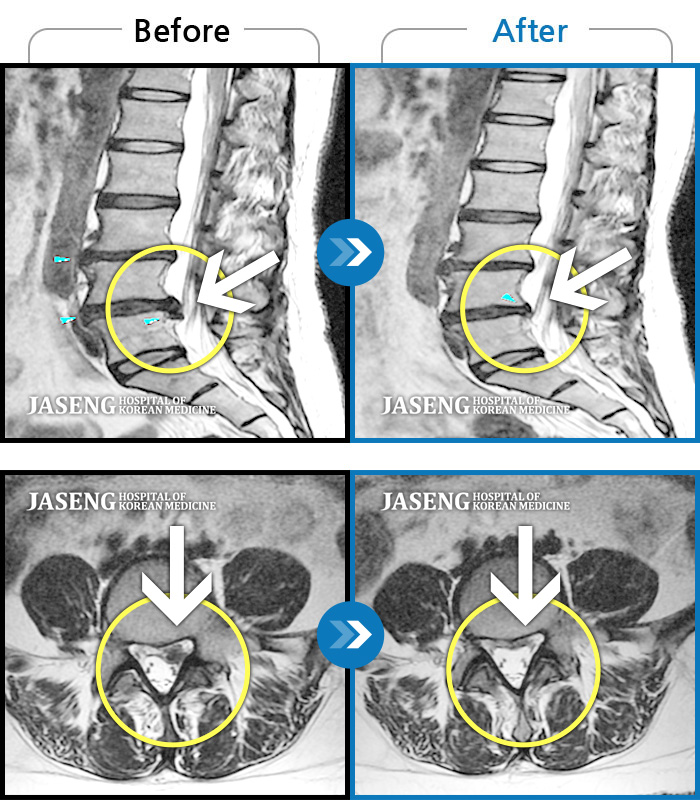

허리디스크

보라매 · 빈상은 원장

엉치에서 좌측 다리까지 통증, 저림으로 움직일 수가 없어요.

촬영시기

2024.08.03 ~ 2025.05.02

2025.12.12

조회수 118